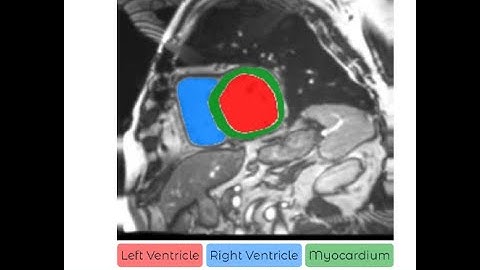

Local Motion Intensity Clustering LMIC Model for Segmentation of Right Ventricle in Cardiac MRI Imag